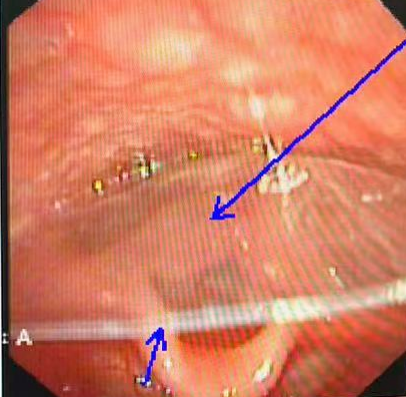

鼻咽镜下的塑料硬膜

随即,儿科与耳鼻喉科团队共同制定多套方案,尝试多种路径接近异物:大号鼻咽镜经口操作因患儿反应强烈难以推进;直接喉镜下又因塑料膜透光难以定位……就在抢救陷入僵局时,转机出现。沈玉才主任医师借助经鼻鼻咽镜进行精确定位,同时在直视喉镜辅助下充分暴露患儿咽喉结构。关键时刻,他眼疾手快,精准夹住塑料膜,将其完整取出。异物取出后,患儿呼吸立刻恢复平稳,现场所有医护人员悬着的心终于放下。